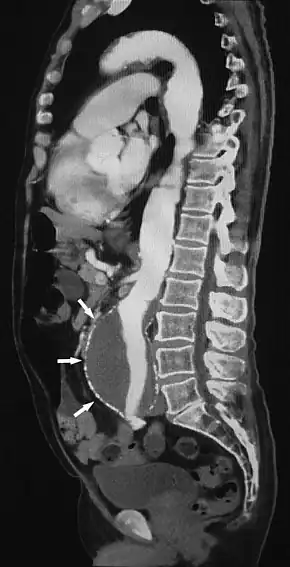

![]() Sagittal thin slice of a computed tomography angiography abdominal aortic aneurysm (AAA) (arrows) | |

Aorta and great arteries

CTA can be used in the chest and abdomen to identify aneurysms in the aorta or other major blood vessels. These areas of weakened blood vessel walls that bulge out can life-threatening if they rupture. CTA is the test of choice when assessing aneurysm before and after endovascular stenting due to the ability to detect calcium within the wall.[3] Another positive of CTA in abdominal aortic aneurysm assessment is that it allows for better estimation of blood vessel dilation and can better detect blood clots compared to standard angiography.[4]